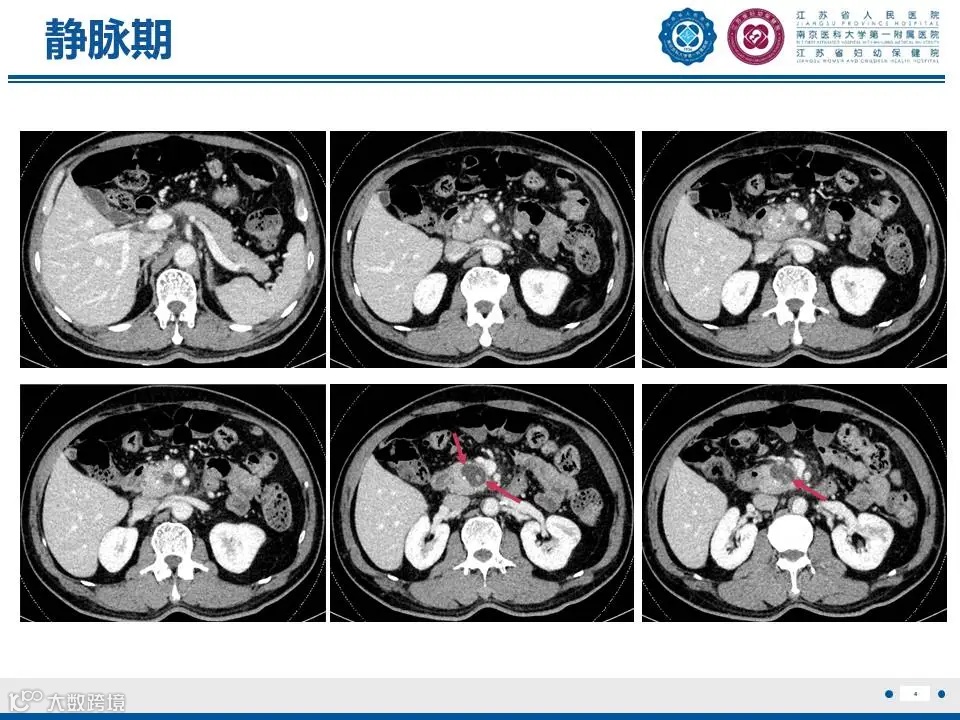

来源:江苏省人民医院放射科